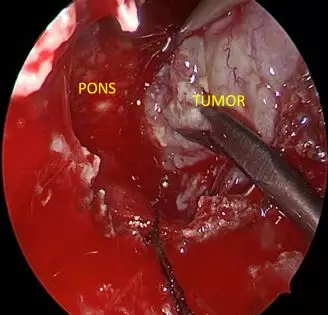

• Tumor embedding brainstem appeared

• After tumor removal,brainstem